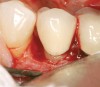

Figure 11  Very large osseous lesion exposed on tooth No. 22 after scaling and degranulation.

Figure 11

Figure 12  Radiographic view of the case seen in Figure 11.

Figure 12